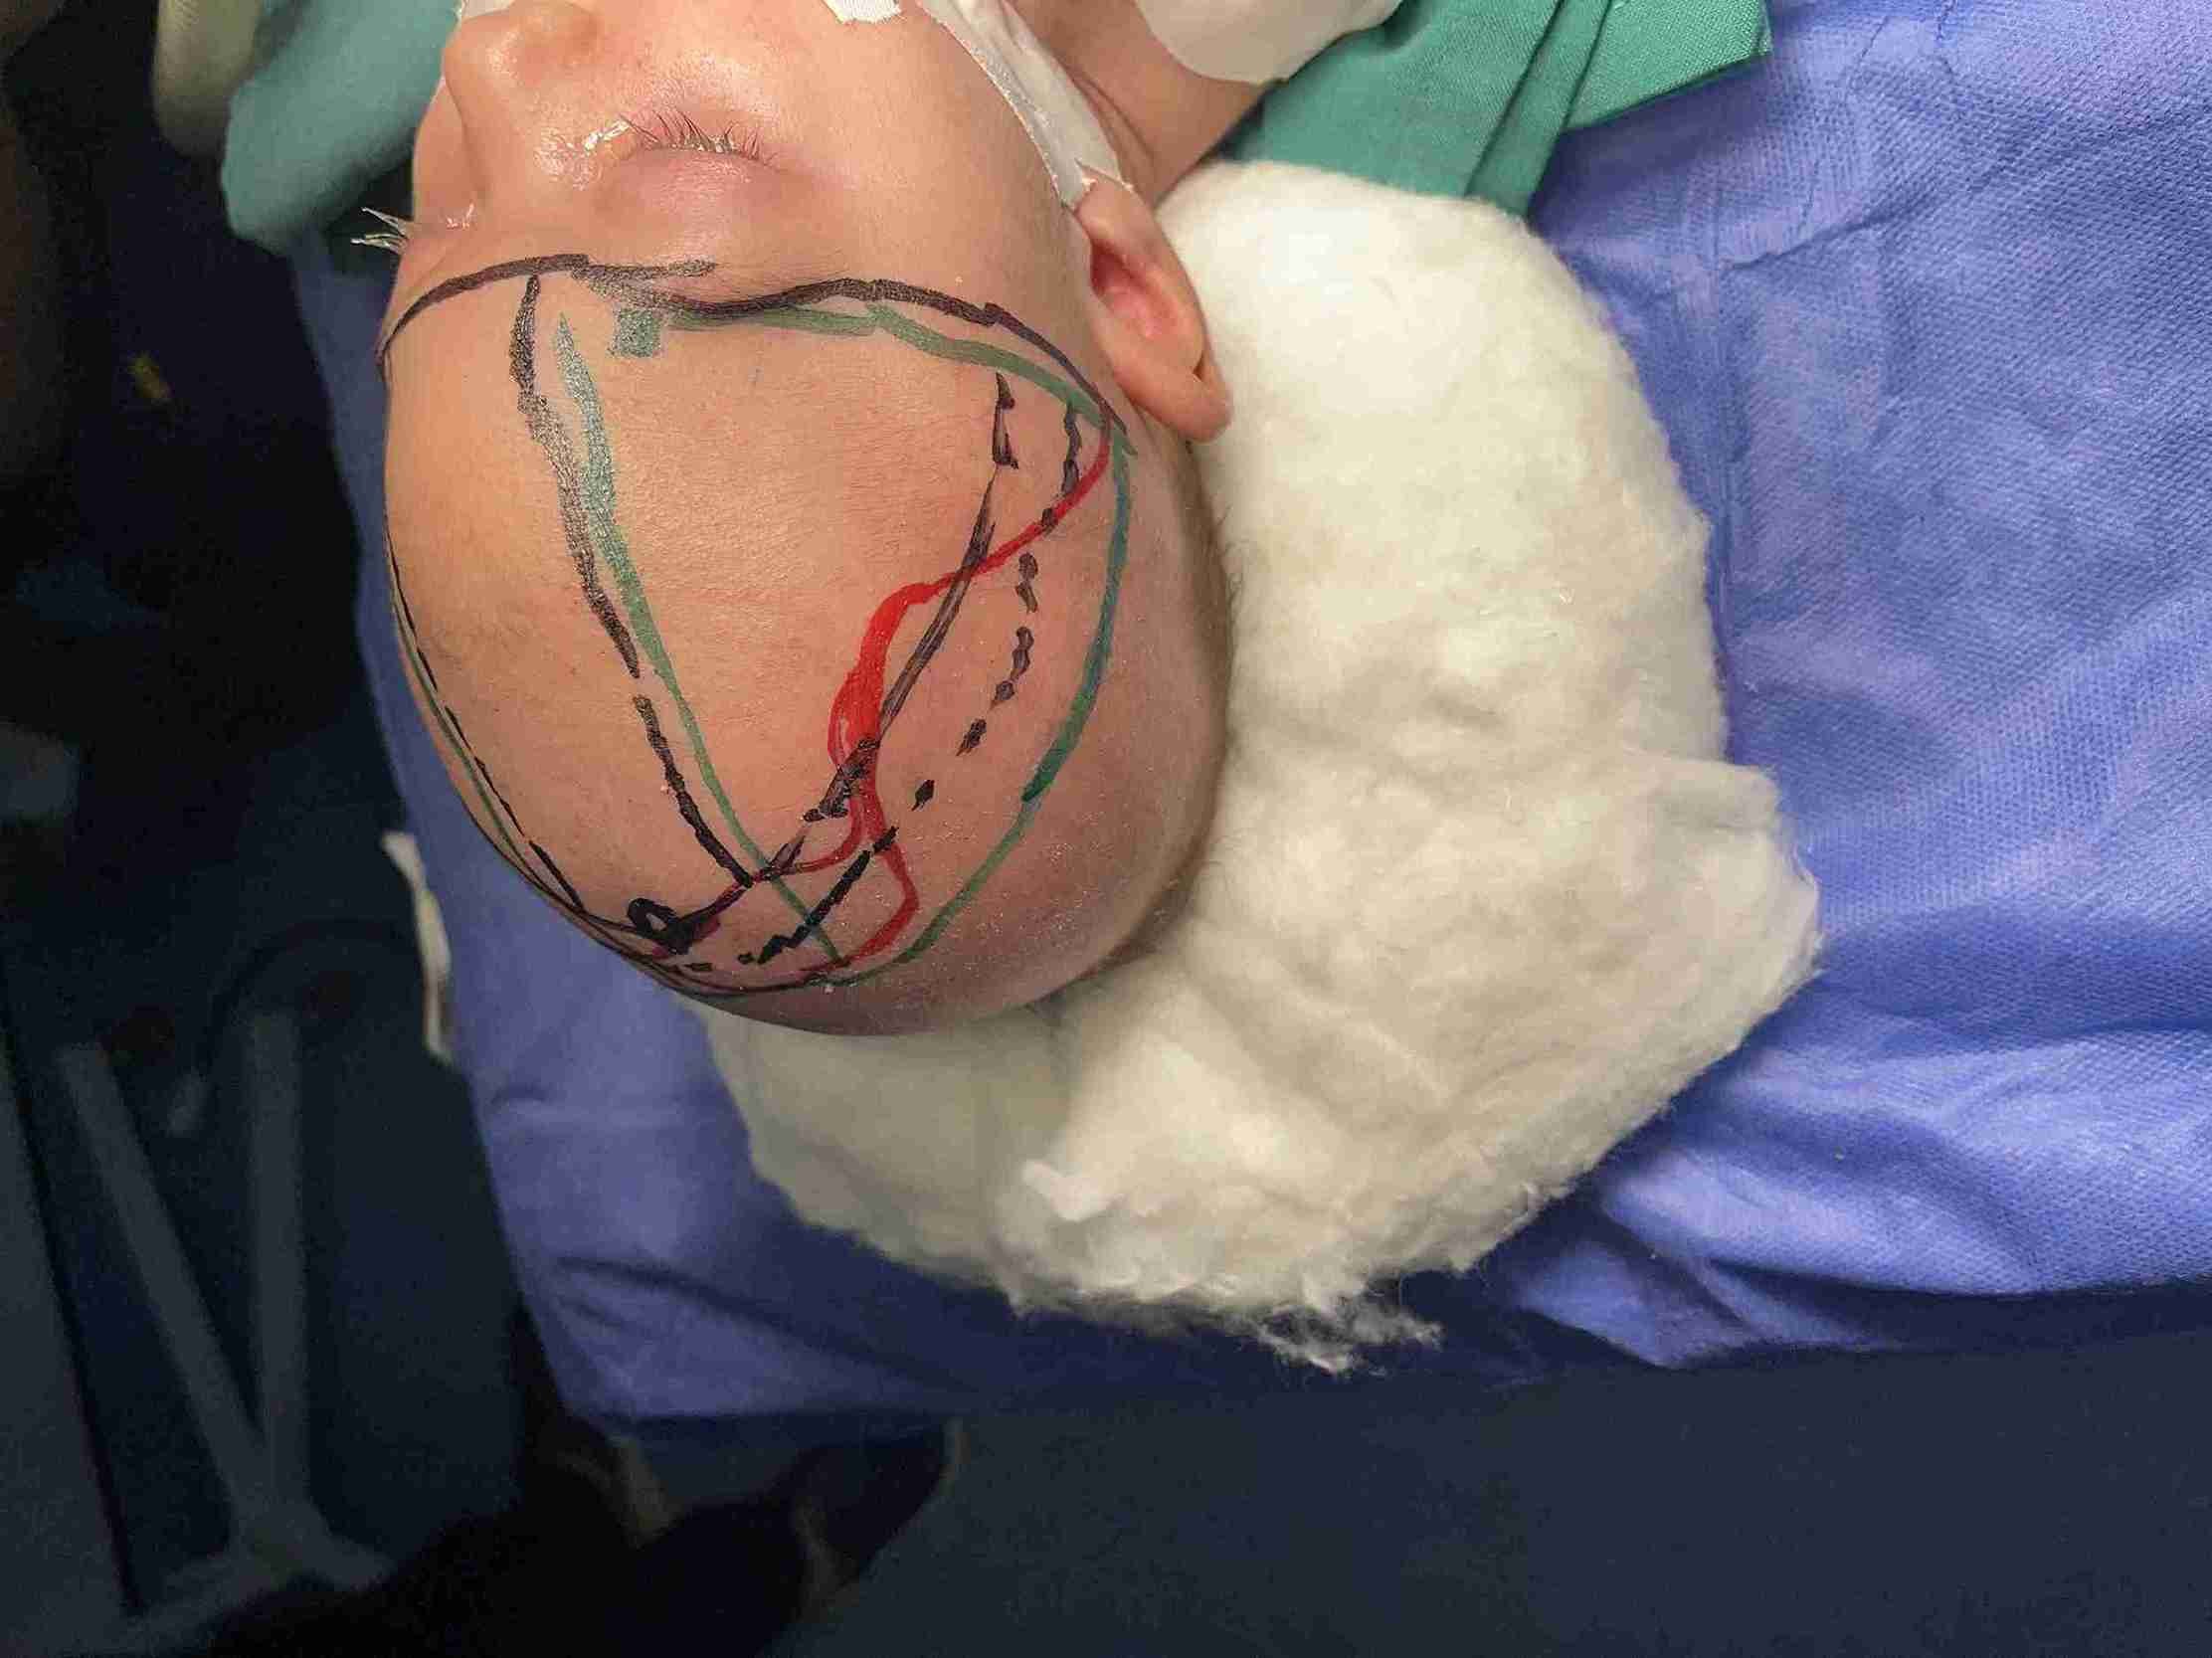

Trigonocephaly Correction Surgery in a Two-Month-Old Infant

A successful cranial correction surgery was performed on a two-month-old infant suffering from trigonocephaly, a condition characterized by a triangular-shaped head. This type of cranial deformity results in a triangular head appearance with a prominent forehead ridge. The goal of the surgery was to correct the skull shape to ensure normal brain development and protect the child from future complications.

• Reshaping cranial bones to correct triangular form

• Removing prominent forehead bony ridge

• Use of latest safe surgical techniques for infants

• Comprehensive approach with multidisciplinary team